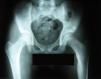

Se solicitaron radiografías de rodilla y pelvis. Las primeras fueron normales, pero en la metáfisis femoral, cercana a la cadera izquierda, se evidenciaba una osteopenia regional y una lesión con marcada esclerosis cortical y nidus central, compatibles con un osteoma osteoide (figura 1). El estudio con tomografía computarizada (TC) confirmó la presencia de un nidus de 5,4mm (figura 2). Se solicitó una consulta con el Servicio de Traumatología de nuestro hospital, que realizó una resección del nidus. El estudio anatomopatológico confirmó el diagnóstico. Cuatro meses tras la intervención, el paciente está asintomático y la movilidad de ambas caderas es normal, aunque persiste una discreta atrofia en el muslo izquierdo, con un perímetro 2cm menor.

Figura 1. Radiografía de pelvis. Osteopenia regional en la cadera izquierda, esclerosis cortical y nidus central (señalado por una flecha).